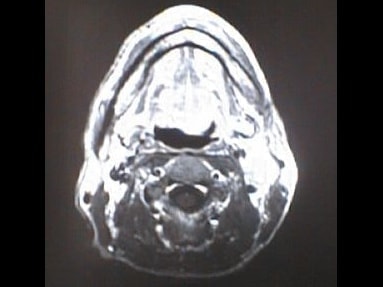

MRI画像比較

中咽頭末期がんMRI画像①

入院当時MRI画像①

中咽頭末期がん消滅時MRI画像①

入院3か月後癌消滅MRI画像①